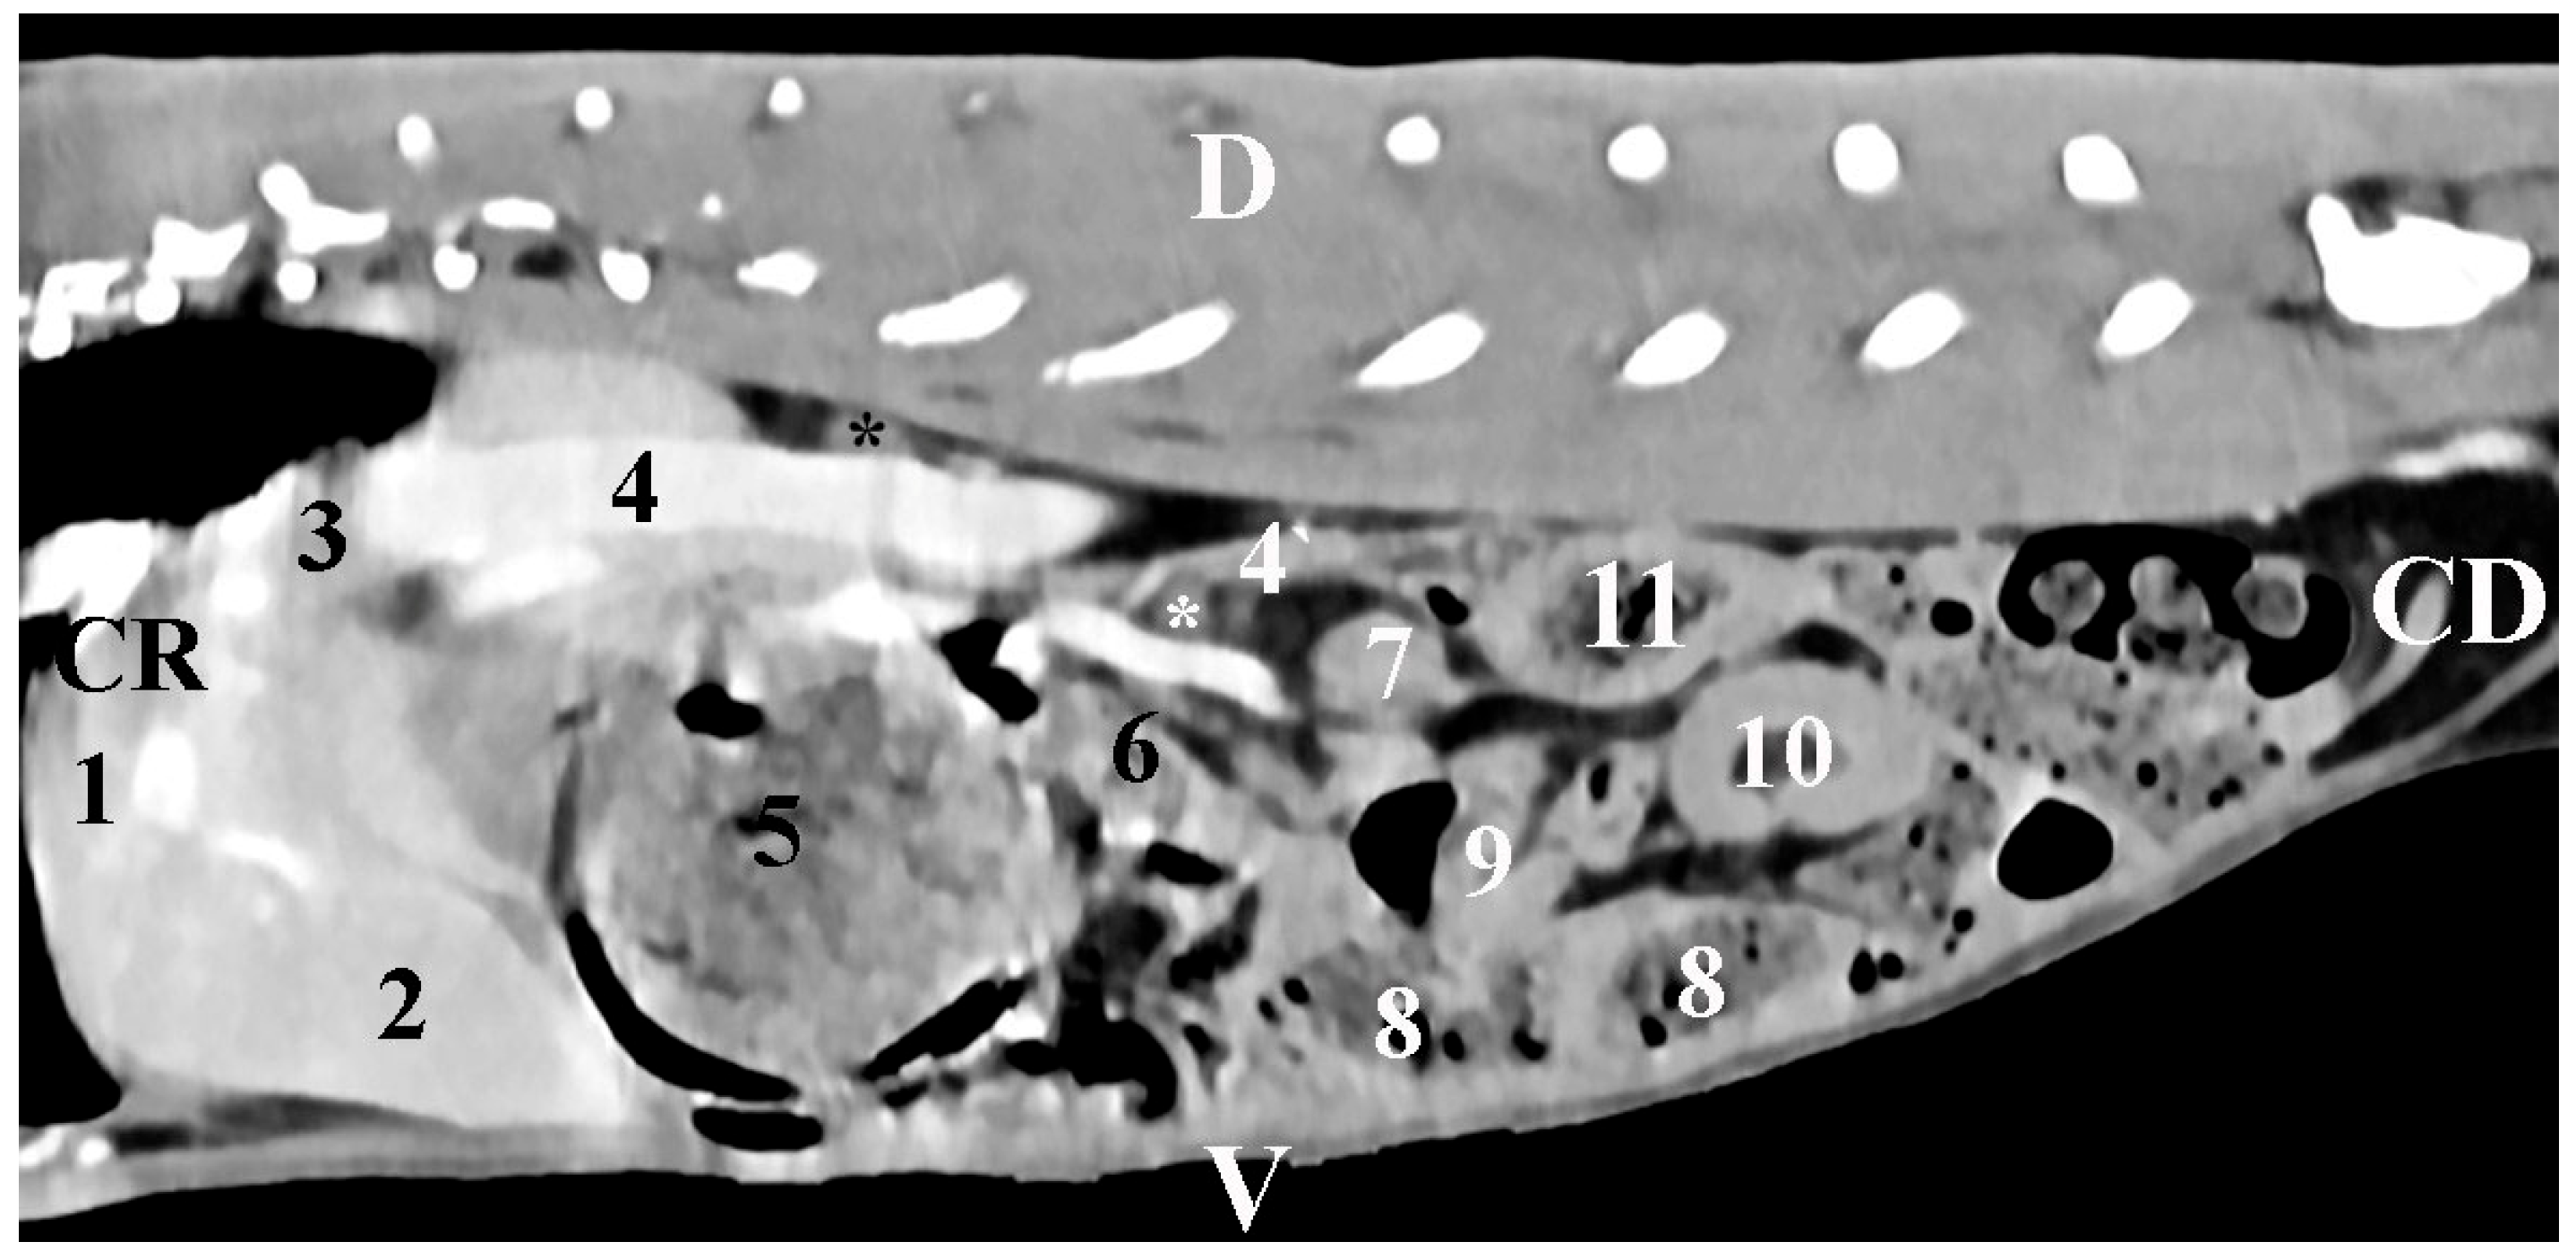

The sagittal post-contrast anatomical study of regio abdominis in the plane 10 mm right to the median plane provided data about the retroperitoneal topographic location of the gl. adrenalis dextra in the regio abdominis lateralis dextra. The right adrenal gland appeared as an ellipse-shaped soft tissue finding in close proximity to the relatively contrast-enhancing v. cava caudalis. The gland was observed cranially to the right kidney. Pars descendens duodeni findings were found ventrally to the gland (Figure 3).

Figure 3. Sagittal CT post-contrast anatomical study of the rabbit abdomen at the level of the plane at 10 mm to the right of the spine. CR—cranial; CD—caudal; D—dorsal; V—ventral. (Black star) right adrenal gland; (white star) mesenterial fold; (1) lobus hepatis dexter; (2) lobus hepatis sinister medialis; (3) lobus caudatus; (4) v. cava caudalis; (4`) v. mesenterica cranialis; (5) corpus ventriculi; (6) pars descendens duodeni; (7) right kidney; (8) caecum; (9) jejunum; (10) colon descendens; (11) colon ascendens.